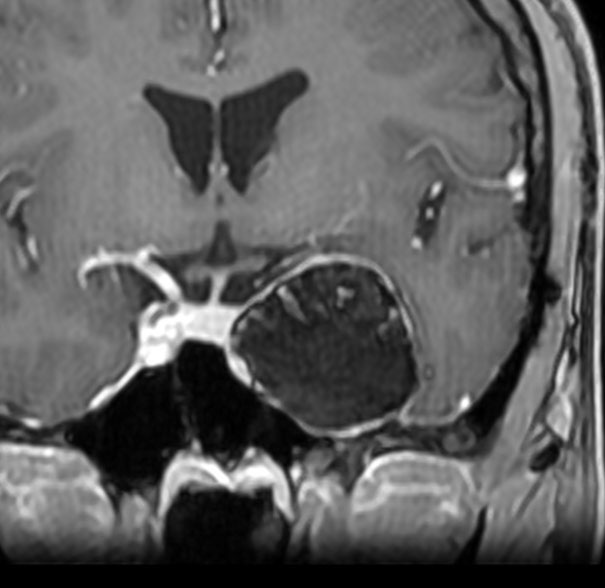

前頭蓋底類皮のう胞

蝶形骨平面から鞍結節上に発生するもので多いタイプです。左側のT2強調画像で内容物がまだらに見え,右側の拡散強調画像で高信号(白い)に見えるので診断確定です。内頸動脈や前大脳動脈や穿通枝などとの癒着が強いものが多いので剥離は難しく要注意です。ある程度の大きさを超えると経鼻内視鏡手術では摘出できません。この腫瘍は脳槽内にあるので,一回の手術でのう胞の壁も含めて全部摘出しなければなりません。そうしないと,手術後に内容物(皮脂と汗とケラチン)が髄液の中に産生されて漏れ出て,難治性の水頭症になります。